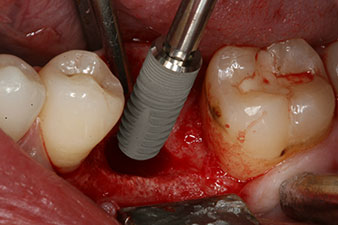

Cependant, six semaines après l’extraction on observe une ossification incomplète après la préparation du lambeau mucopériosté dans la région de l’ancienne alvéole mésiale.

L’implant a été posé comme prévu après élimination complète du tissu de granulation (blueSky, bredent).

Le couple utilisé pour la pose guidée était de 43 Ncm.